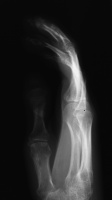

Clinical Example: Scleroderma, Calcinosis and Acroosteolysis

Scleroderma is a polymorphic condition , variably associated with a variety of conditions including joint stiffness, subcutaneous calcification and acroosteolysis. This patient with scleroderma demonstrates all of these conditions. This is most commonly associated with the finding of anticentromere antibodies.